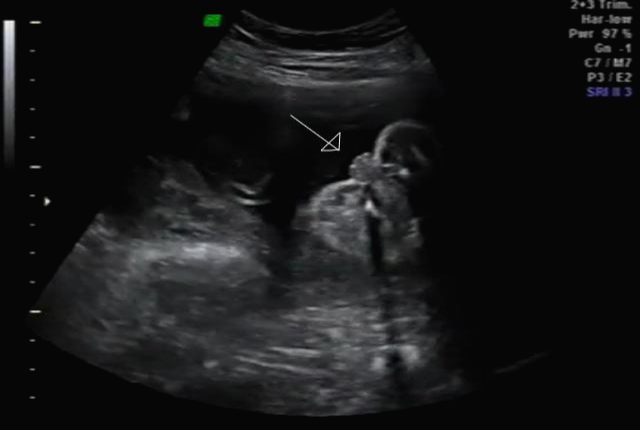

한 달 뒤인 17차 때 다시 사설로 가서 초음파 검사를 받았는데 검사해주시는 분 께서 한참을 보시더라고요~ 그러면서 어떻게 보면 딸 같다고 하셔서... 응? 100프로 아들이라 해서... 다 아들껄로 준비하고 있는데.. 무슨 소리지? 하고 다시 한번 봐달라고 하니 아들이라 하시면서 위에 초음파를 보여주셨어요!